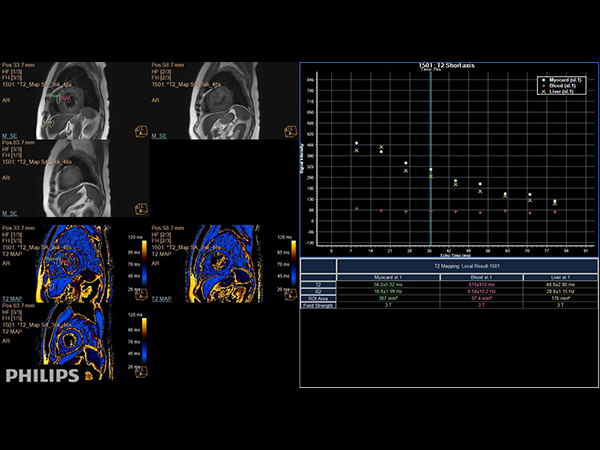

Short axis view T2 Map

Short axis view (T2 Mapping on ISP 12)